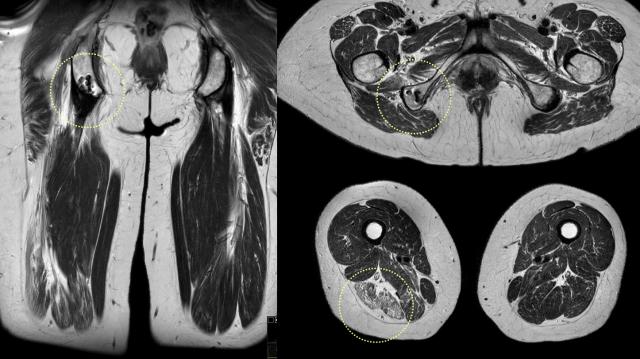

Hình ảnh này cho thấy tổn thương một phần gân chung của chân phải (vòng tròn vàng).

Có một lượng lớn máu tụ xung quanh trong cơ và dọc theo mạc cơ.

Phù nề bao quanh dây thần kinh tọa (mũi tên vàng), có thể dẫn đến bệnh lý thần kinh.

Tuy nhiên, có sự tương quan kém giữa các hình ảnh trên MRI và các triệu chứng lâm sàng của bệnh nhân.

Trong trường hợp này, tổn thương một phần ít rõ ràng hơn. Tuy nhiên, dây thần kinh tọa vẫn bị phì đại và dẹt do phù nề từ tổn thương.

Tất cả các đặc điểm gợi ý tổn thương thần kinh đều được ghi nhận (bao gồm: phì đại dây thần kinh, dẹt dây thần kinh, phù nề trong dây thần kinh, phù nề xung quanh hoặc xơ hóa xung quanh).

Sau chấn thương, gân có thể trở về hình ảnh bình thường sau khi lành. Tuy nhiên, trong hầu hết các trường hợp tổn thương một phần, sẹo xơ hóa thường được ghi nhận tại vị trí chấn thương cũ (vòng tròn chấm vàng).

Khá thường gặp trường hợp khi chụp MRI vì một chấn thương cấp tính, các vị trí xơ hóa sẹo của những chấn thương cũ hơn cũng được phát hiện đồng thời.